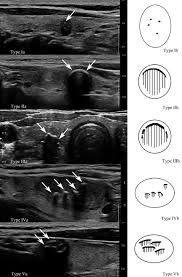

Risk factors that may be changed radiation. In fact, it is the 8th most common cancer among women overall and the most common cancer in women younger than 25. In fact, certain characteristics are typical of thyroid cancer and these characteristics can help guide diagnosis and further management (11). Hypothesis ultrasonography is useful for predicting malignancy of thyroid nodules. However, fewer than 2000 patients die of thyroid cancer each year.

Characteristics Of Thyroid Cancer Moe from www.env.go.jp Therefore, ultrasound and fine needle aspiration (fna) are integral in cancer screening. This study aims to review the clinical and histopathological characteristics of tc in saudi arabia and analyze the size trend over the years. Thyroid cancer is relatively uncommon compared to other cancers. Most commonly, papillary thyroid cancers are totally asymptomatic. Thyroid cancer develops when cells change or mutate. Only a small percentage of thyroid nodules are cancerous. Staging the tumor helps your doctor determine the best treatment for your thyroid cancer. Design a retrospective study of 329 thyroid nodules (≥5 mm) in 309 patients comparing us characteristics and pathological results.